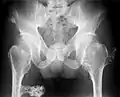

Multiple osteochondromas at the pelvis